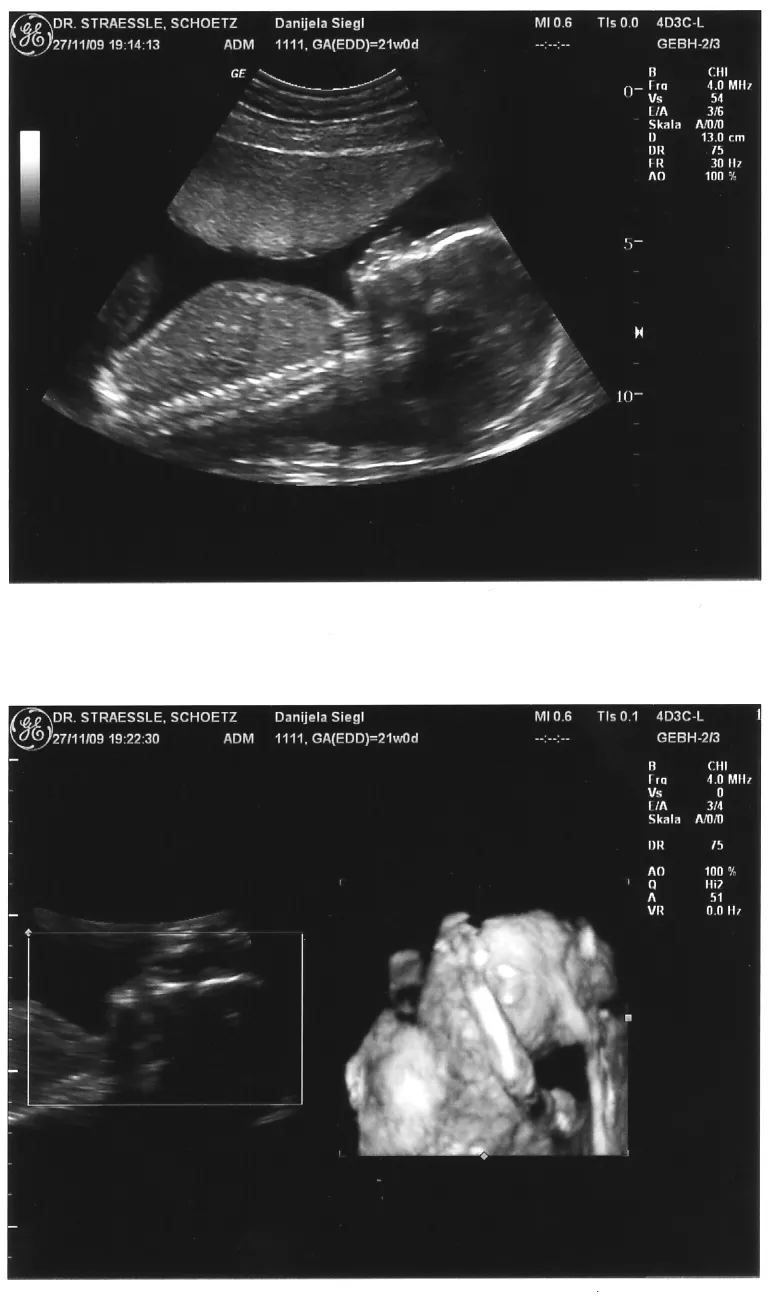

ja wir waren am Freitag beim Baby-watching

der Doc meinte er kann es noch nicht genau sagen ob es boy oder girl wird - ich hab aber alles gefilmt und mehrmals angeschaut und ich denke mal bei einem Jungen müsste man was zwischen den Beinen sehen - da war aber nix

schaut ganz nach Mädchen aus :)

das rechts ist ein 3D-Bildt, leider hält "es" sich gerade die Hand vors Gesicht - wollte wolh nicht gesehen werden :lol:

sieht ech süss aus...nochmals glückwümsche:!: